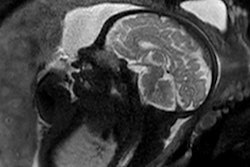

Sagittal images of a normal brain. mTIs nulling white matter (A), mTIi nulling gray matter (B), SIR (mTIs -- mTIi) in (C) and rSIR (mTIi -- mTIs) in (D). There is high gray white matter contrast with gray matter high signal and white matter low signal in (C). In (D) the gray white matter contrast is reversed with white matter white, and gray matter black. Cerebral spinal fluid is of intermediate signal near the noise level in both (C) and (D). SIR, subtracted inversion recovery; TI, inversion time; rSIR, reversed subtraction inversion recovery. Image courtesy of Drs. Ya-Jun Ma, Hongda Shao, Shujuan Fan, Xing Lu, Jiang Du, Ian R. Young, and Graeme M. Bydder and Quantitative Imaging in Medicine and Surgery, October 2020.The tissue properties-filters approach, on the other hand, treats pulse sequences as filters of tissue properties and shows them in graphical form, including the voxel signal S, the contrast, and the sequence weighting (slope of the filter) for each tissue property.